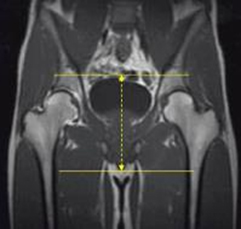

COR T1 TSE 3-4 mm 0.5-1mm None both hips 1cm anterior to symphysis pubis thru both ischial tuberosities

COR T2 STIR (TE=50-60) TSE 3-4 mm 0.5-1mm STIR both hips 1cm anterior to symphysis pubis thru both ischial tuberosities

MRI Pelvis Sports Hernia WO MSK Protocol image 4